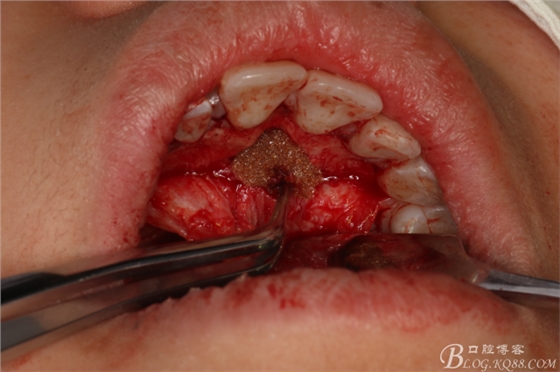

圖16.拔除兩顆多生牙后的鼻腭管情況

圖17.拔牙創(chuàng)口放置膠質(zhì)銀兩枚